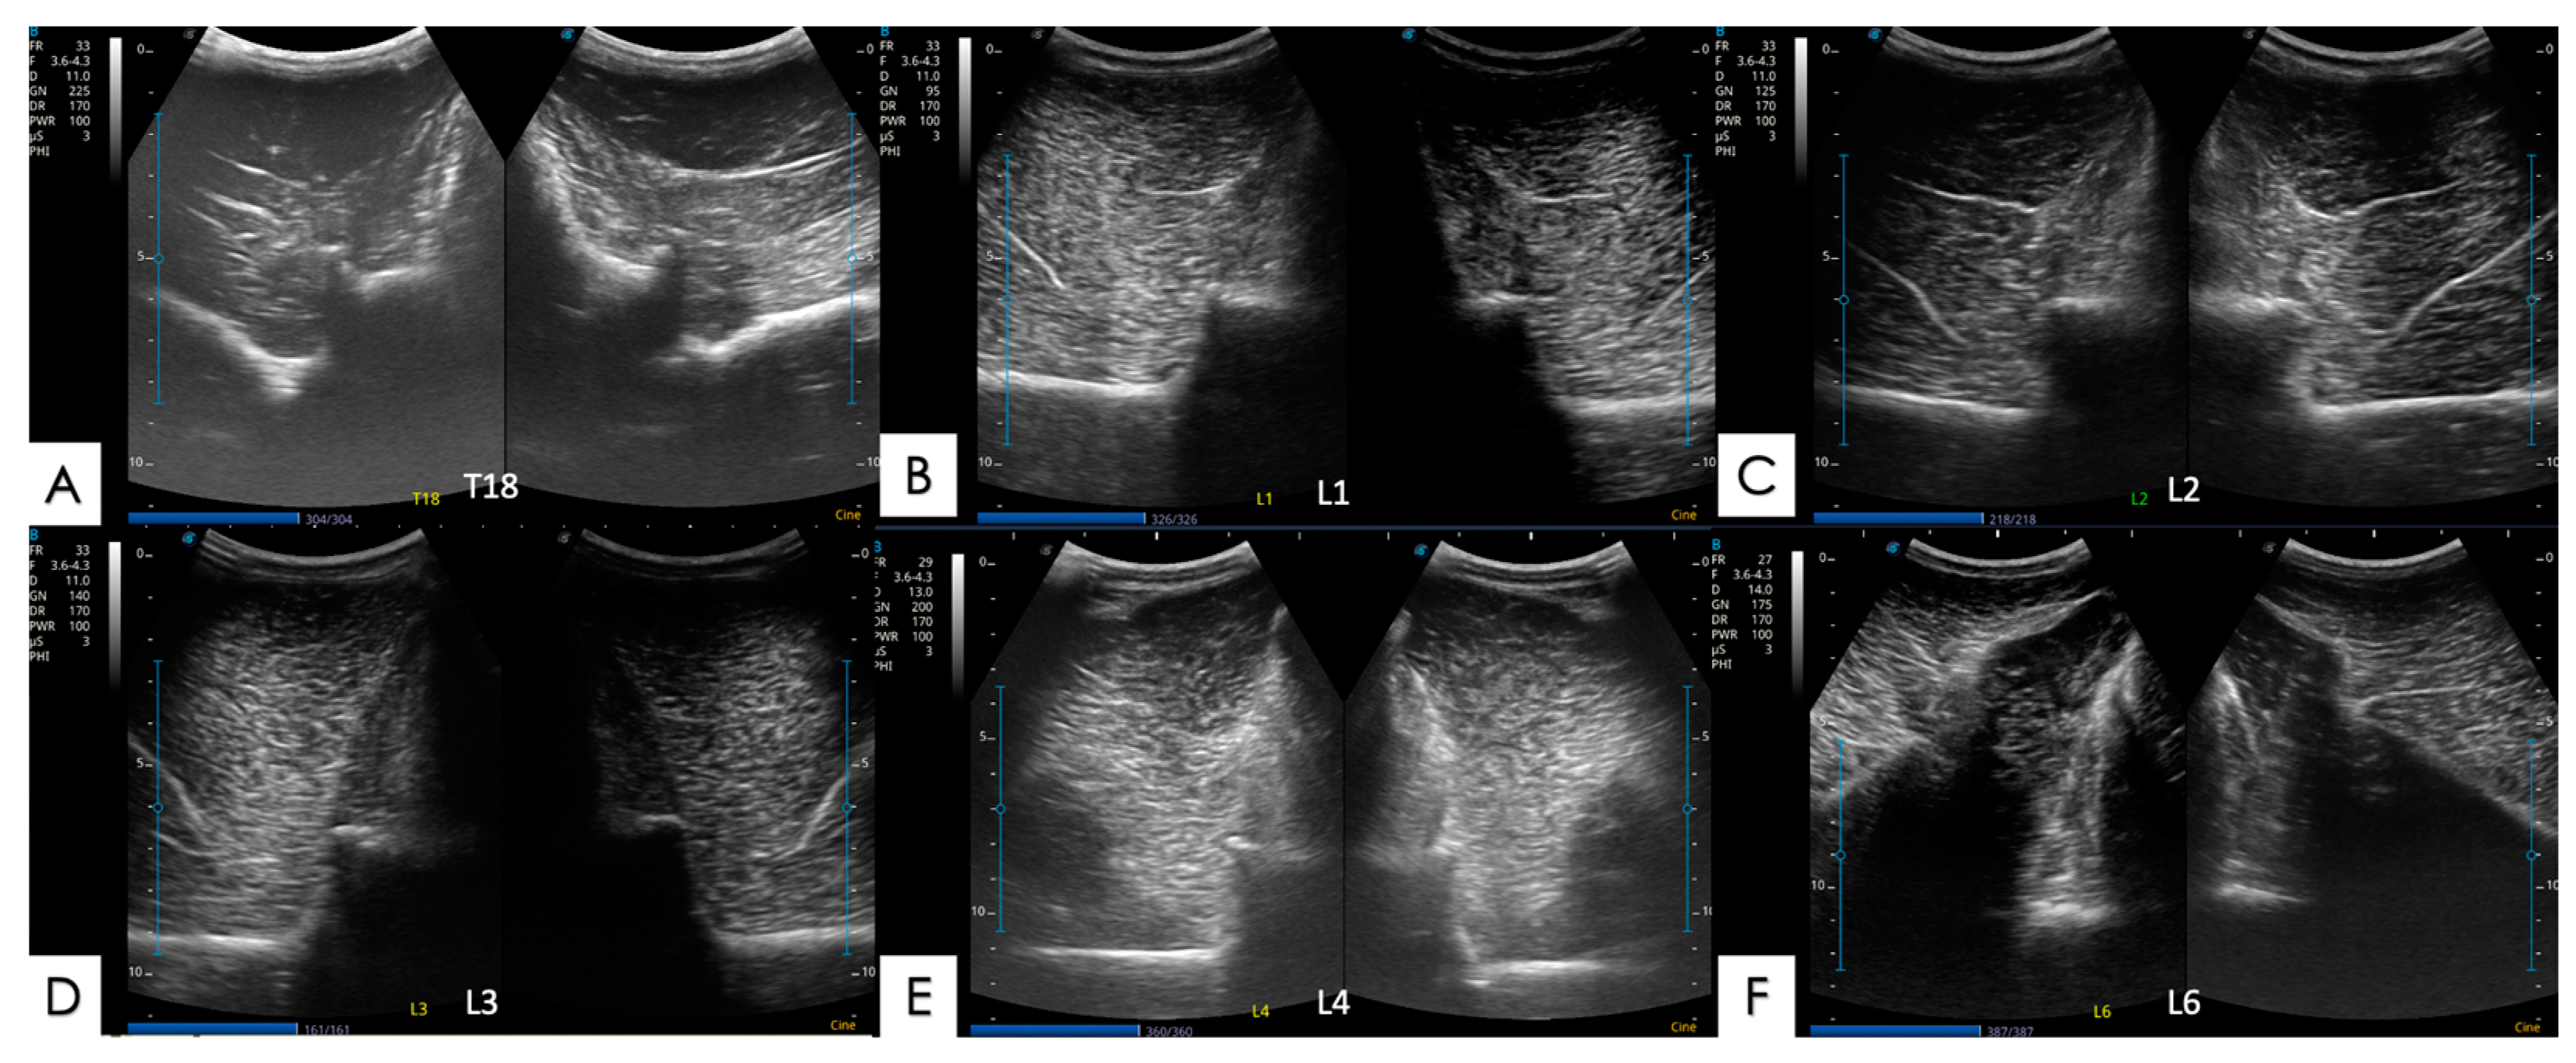

2.5.1. Articular Processes and Epaxial Muscle

2.5.2. Spinous Processes and Supraspinous Ligament